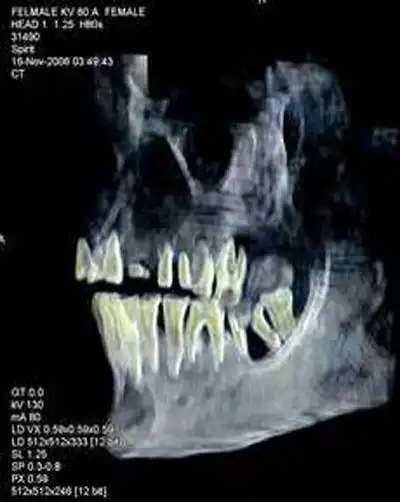

Одно из исследований состояло в сканировании деревянного ящичка с именем Хатшепсут - в нем оказались человеческие печень и зуб. Зуб, как сообщил Хавасс, идеально подходит к лунке в челюстной кости "толстой женщины" и совпадает со сломанным корнем. Кроме того, была изучена митохондриальная ДНК, наследуемая только по материнской линии. У предполагаемой Хатшепсут она указывает на родство с первой царицей XVIII династии Ахмосе-Нефертари.